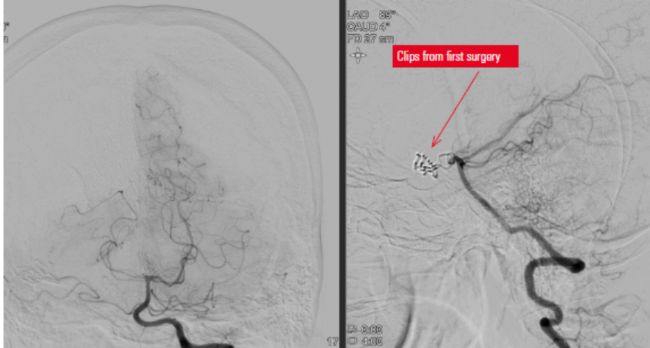

圖1:初次手術后的CT影像。

圖像由巴西圣保羅聯(lián)邦大學(UNIFESP)血管神經(jīng)外科主任Chaddad博士(教授)提供。